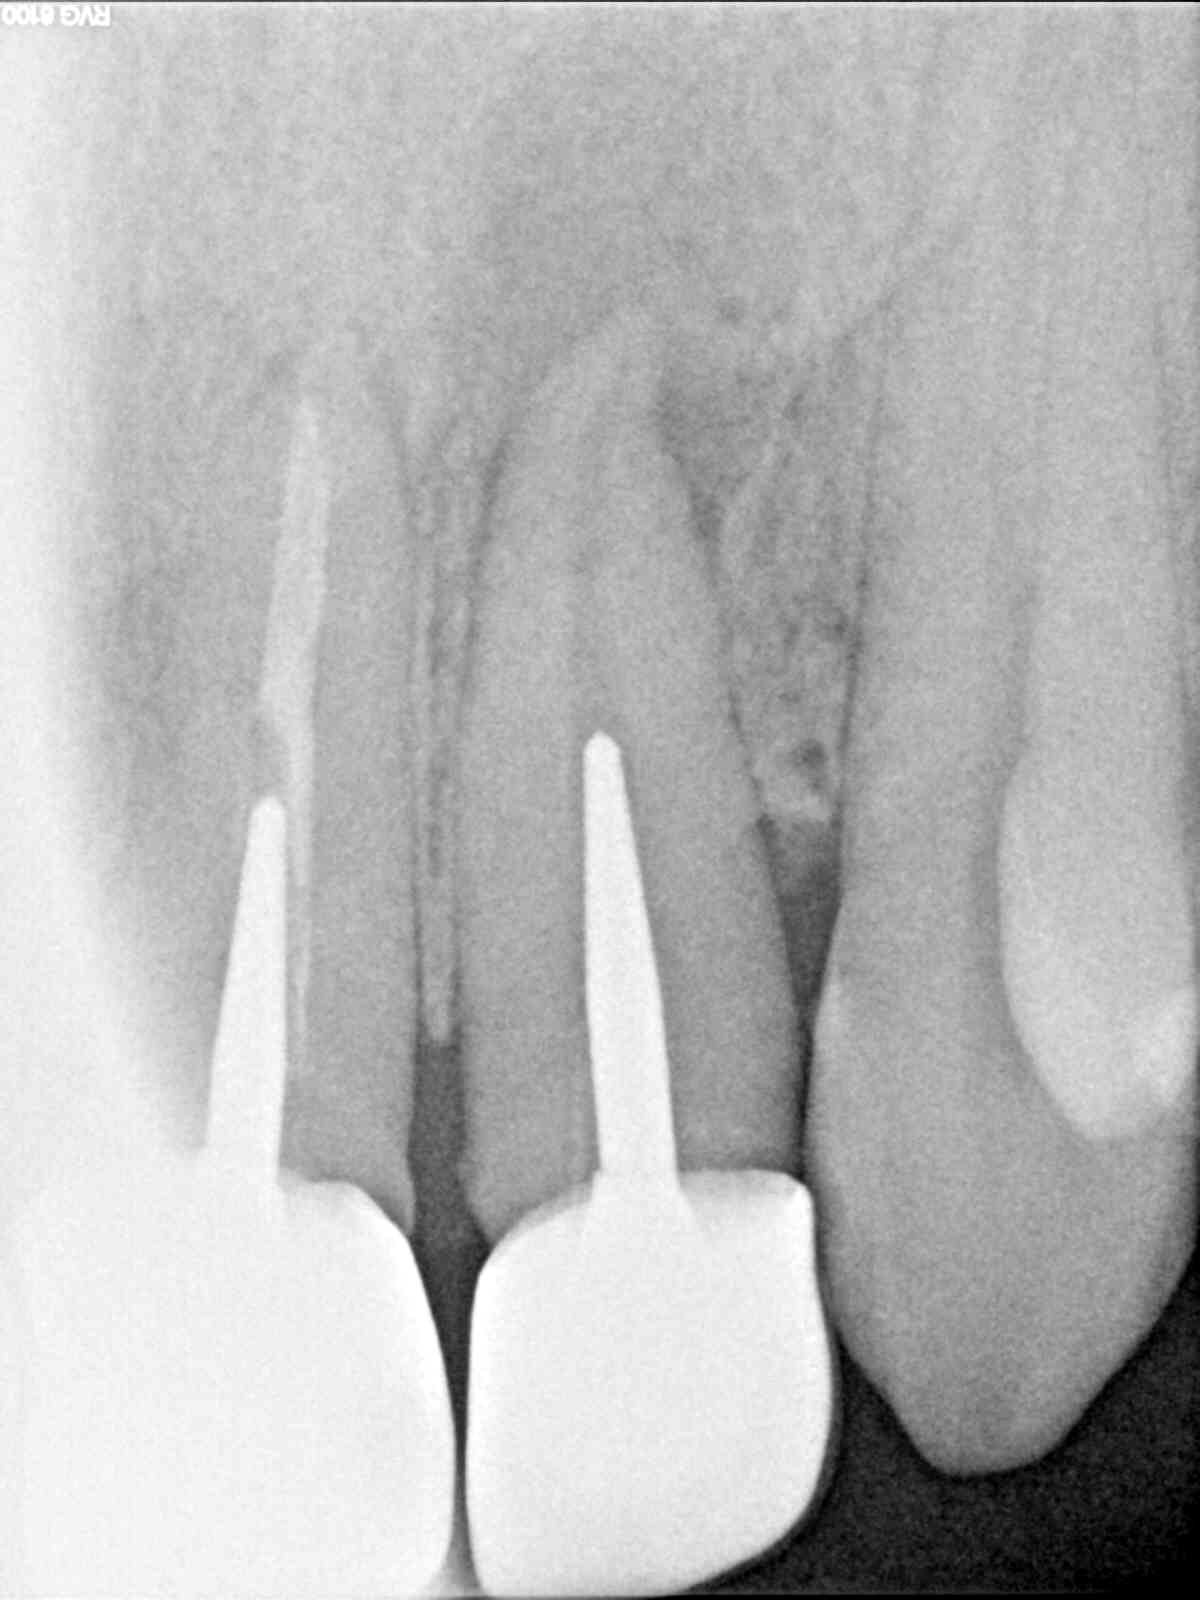

Mon petit cas , une 22 avec un abcès palatin récidivant depuis des années et pour cause ...pas d'obturation sous une couronne , les rd datent de début décembre , fin janvier , fin mai . tutti va bene , plus de trace de rien au palais

Alors j'ai fais l'endo début janvier , ça allait mieux , mais il restait toujours une petite tuméfaction au palais , je me suis dit vas-y casa tu l'as déjà fait ...! donc fin janvier , j'ai extrait le dent , retouché un peu l'apex , un petit crochet inesthétique ! ,cureté le fond de l'alvéole ..et j'ai remis avec une provisoire sans contention rien ... j'ai vérifié en Mars je crois , tout allait bien , plus rien au palais , en mai j'ai fait la définitive ....impeccable ! aucune mobilité gencive impeccable !

La radio initiale .